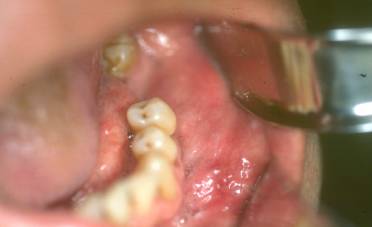

Al examen intrabucal se observa lesión de naturaleza tumoral que se presenta en el cuerpo del maxilar inferior lado izquierdo y se extiende desde canino hasta la región molar. Fig. 2

Figura 2. Imagen clínica intrabucal